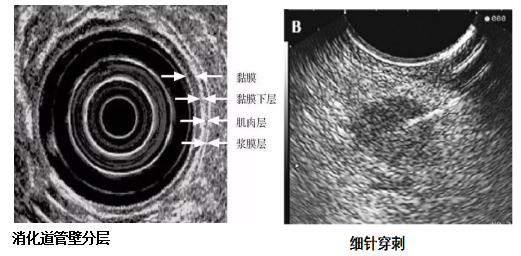

消化道超声内镜检查(,EUS)是通过安装在内镜先端或经由内镜插入的超声探头进行实时扫描,可以在内镜观察消化道腔内形态的同时获得消化管壁层次以及周围邻近脏器的声学特征。由于兼具内镜和超声功能,EUS被称为内镜医生的第三只眼。

EUS可开展项目:1.对消化道肿瘤进行术前分期;2.对粘膜下肿物判断性质及来源;3.对消化道周围脏器及组织进行超声检查,比如后纵隔疾病、胆胰疾病、盆腔疾病、肝左叶疾病等;4.对EUS探及病变进行病理穿刺细胞学或组织学检查;5.对EUS探及病变进行注药治疗。